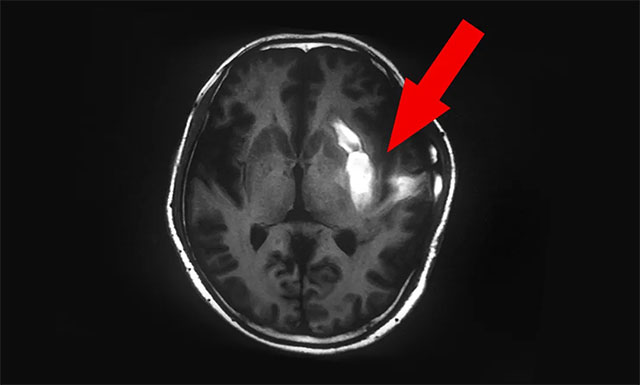

腦出血部位臨近功能區(qū),致使患者右側(cè)肢體偏

▲ 腦出血部位臨近功能區(qū),致使患者右側(cè)肢體偏癱